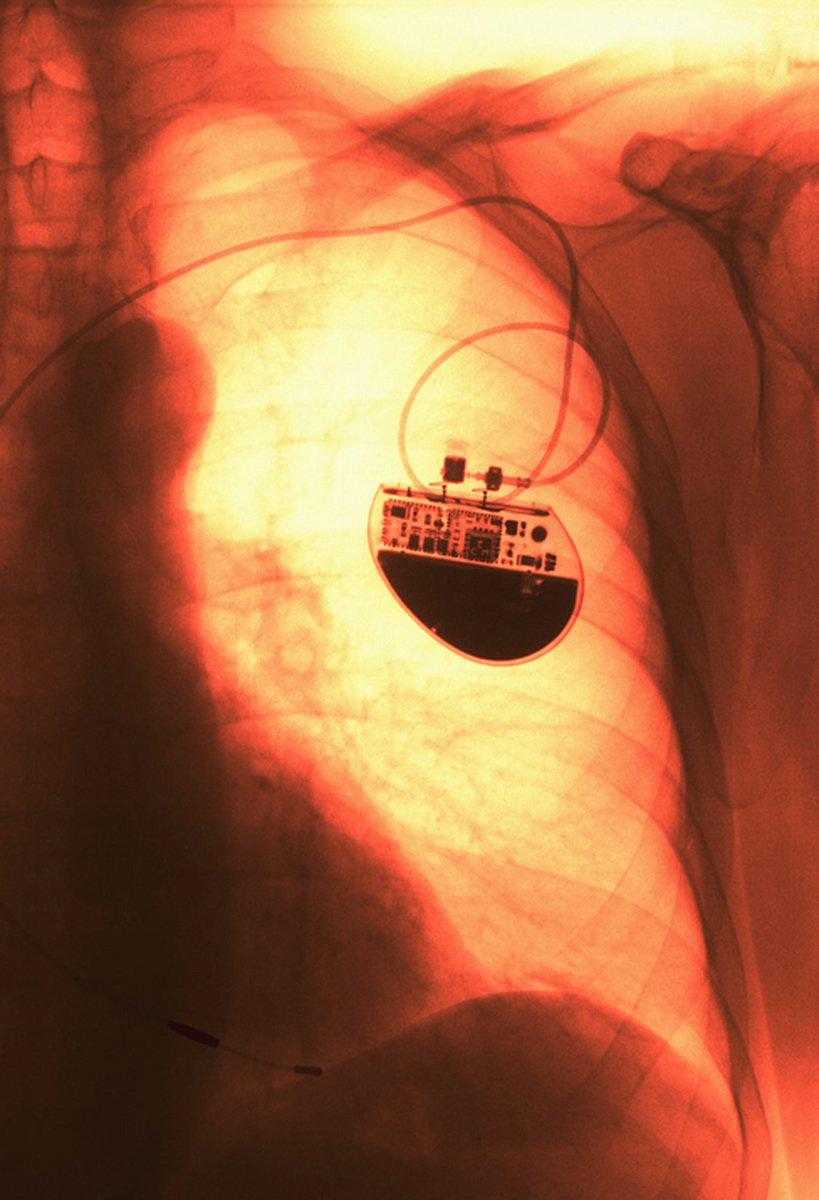

🟣 How do we ensure safety and effectiveness of #bioelectronic devices & judge when they are truly necessary for the rehabilitation of neurological conditions? ask #RDBioelectronics EiC Prof. Samit Chakrabarty @sc_laboratories et al. Find out more here: bit.ly/3nXCtEt

🟣 How do we ensure safety and effectiveness of #bioelectronic devices & judge when they are truly necessary for the rehabilitation of neurological conditions? ask #RDBioelectronics EiC Prof. Samit Chakrabarty @sc_laboratories et al. Find out more here: bit.ly/3nXCtEt

🟣 How do we ensure safety and effectiveness of #bioelectronic devices & judge when they are truly necessary for the rehabilitation of neurological conditions? ask #RDBioelectronics EiC Prof. Samit Chakrabarty @sc_laboratories et al. Find out more here: bit.ly/3nXCtEt

🟣 How do we ensure safety and effectiveness of #bioelectronic devices & judge when they are truly necessary for the rehabilitation of neurological conditions? ask #RDBioelectronics EiC Prof. Samit Chakrabarty @sc_laboratories et al. Find out more here: bit.ly/3nXCtEt